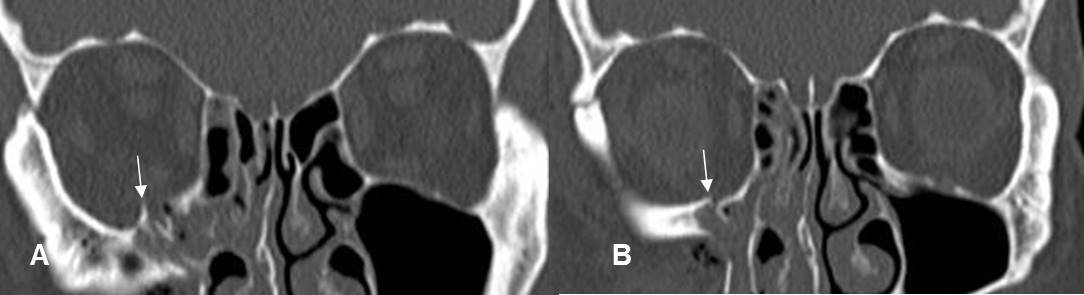

Fig 215 A. Fractura de órbita, sin atrapamiento muscular.

A y B: TAC reconstrucción coronal. Fracturas no deprimidas en el piso de la órbita y sin signos de atrapamiento muscular.

Fig 215 B. Fractura de órbita.

A: TAC coronal en ventana de tejido y B: TAC coronal en ventana de hueso.

Fractura deprimida en el piso de la órbita. Hay herniación de la grasa, pero el recto inferior mantiene su posición. (Flecha gruesa).